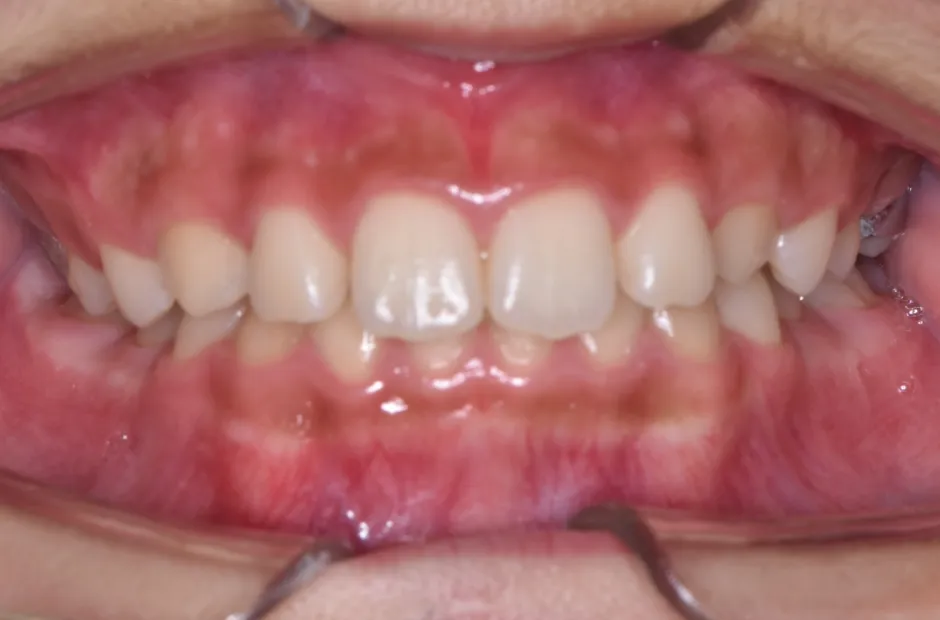

前歯部反対咬合

| 診断名・主訴 | 前歯部反対咬合 |

|---|---|

| 年齢・性別 | 14歳・男性 |

| 治療期間・回数 | 1年2か月 |

| 治療に用いた主な装置 | ブラケット矯正 |

| 抜歯部位 | なし |

| 治療費 | 60万円(税抜) |

| リスク・副作用 | 装置による違和感・疼痛・歯肉退縮・歯根吸収・虫歯のリスクなど |

治療前

治療後